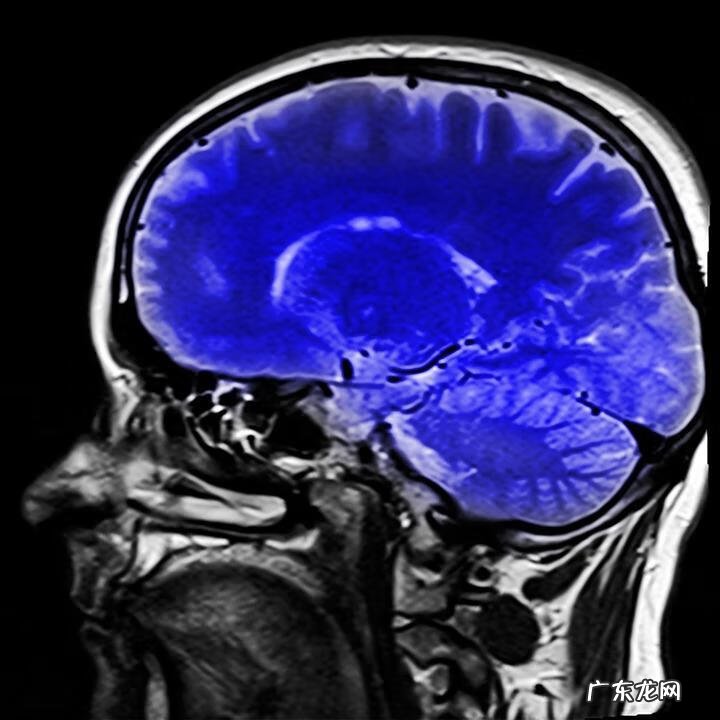

文章插图

磁共振头部成像

目前,在医院有HDR-R(长谷川痴呆修订量表)、磁共振成像装置(MRI)及单光子发射计算机断层扫描(S-PECT)设备影像诊断来对痴呆症进行鉴别 。

占痴呆症7成的阿尔茨海默病是由于β淀粉样蛋白、磷酸化tau蛋白等物质在大脑内蓄积,使大脑萎缩引起 。利用正电子发射断层成像装置(PET)可以检测出这些病因物质 。

这些基于成像技术进行的早期诊断的好处,第1是可以将阿尔茨海默病以外原因导致的痴呆症鉴别出来,这样有利于选择合适的治疗方案 。第2是可以确定异常蛋白是否在脑内某个特定部位蓄积,因为大脑不同部位功能不同,如果可以确定在某个特定部位的话可以知道病人会有什么症状,提供更好的治疗 。